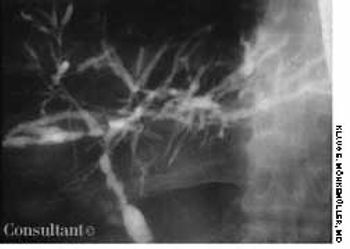

A 45-year-old man presented with a 2-month history of progressive fatigue, weight loss of 10 lb, abdominal pain, and pruritus. The patient had been taking a maintenance dose of oral mesalamine since he received a diagnosis of ulcerative colitis 14 years before.